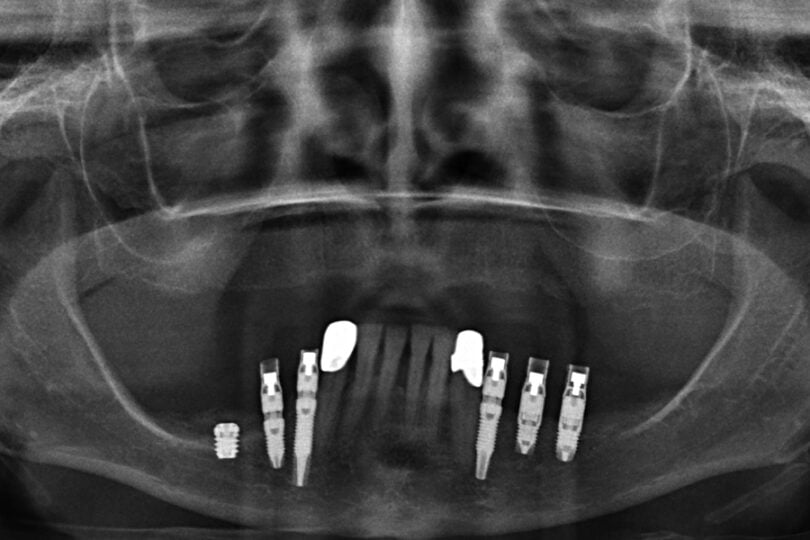

Quatro dos seis implantes foram de 5,5 mm de comprimento por 5 mm de diâmetro, um implante foi de 6,5 mm de comprimento por 3,75 mm de diâmetro e o último implante foi de 6,5 mm de comprimento por 5 mm de diâmetro (figura 2).

Em nenhum caso foram utilizadas técnicas cirúrgicas complementares na cirurgia de implantes e todos os implantes foram realizados em dois tempos cirúrgicos, com um tempo de espera de 3 meses até à carga.

As seguintes imagens apresentam um dos casos incluídos no estudo (figura 03 – 15).